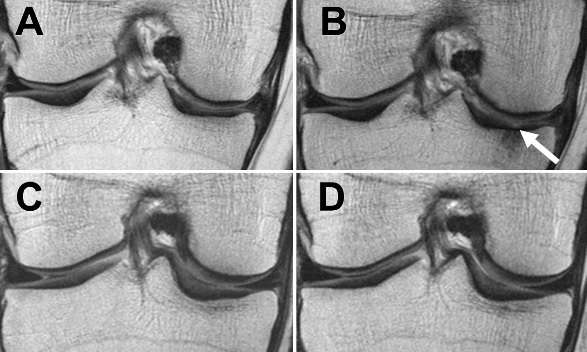

Les chercheurs californiens ont analysé via IRM les différences de dégénérescence de toutes les structures articulaires du genou (ménisques, cartilage articulaire et moelle osseuse) chez 640 patients obèses et en surpoids (IMC>25 kg/m2), dont un groupe « de perte de poids » et un groupe témoin. A l'issue de l'étude, les patients ont été classés en 3 groupes : ceux qui ont perdu plus de 10% de leur poids corporel, ceux qui ont perdu de 5 à 10% de leur poids corporel et un groupe témoin final dont le poids est resté stable.

Perte de poids et réduction de la dégénérescence du cartilage : L'analyse confirme que les participants en surpoids et obèses qui sont parvenus à une perte de poids élevée sur une période de 48 mois ont bénéficié d'un ralentissement significatif de la dégénérescence du cartilage de genou. Précisément,

-les patients avec perte de poids de 5% présentent des taux de dégénérescence du cartilage inférieurs à ceux des participants de poids stable ;

-les patients avec perte de poids de 10% présentent une dégénérescence du cartilage encore ralentie.

-Non seulement la perte de poids ralentit la dégénérescence du cartilage articulaire, mais aussi celle des ménisques, ces coussinets de fibrocartilage en forme de croissant qui protègent l'articulation.